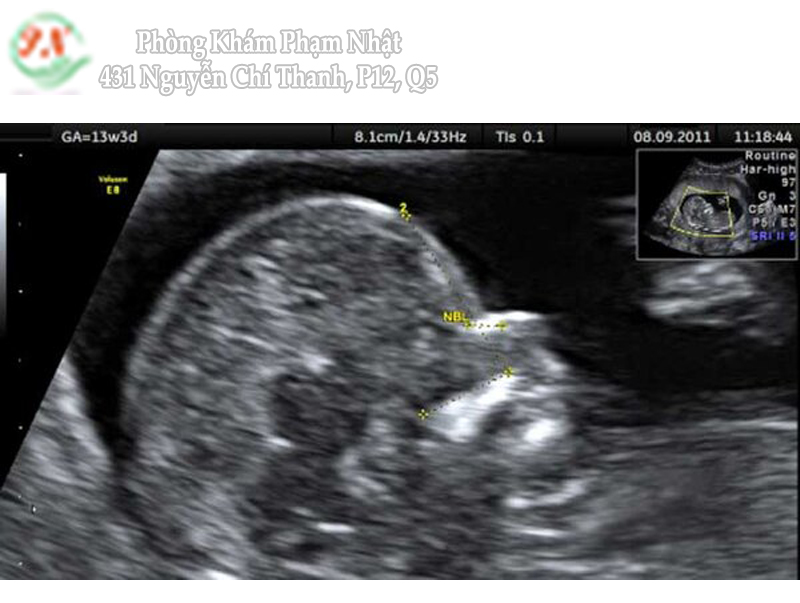

Xương mũi thai nhi

Khảo sát xương mũi thai nhi được kết hợp trong lúc khảo sát và đo NT.

Chiều dài xương mũi ngắn hay không quan sát thấy gặp ở 60% các trường hợp trisomy 21; 50% các trường hợp trisomy 18; 40% trường hợp trisomy 13.

Chỉ 1-3% trường hợp thai không có xương mũi là không có bất thường về số lượng nhiễm sắc thể.